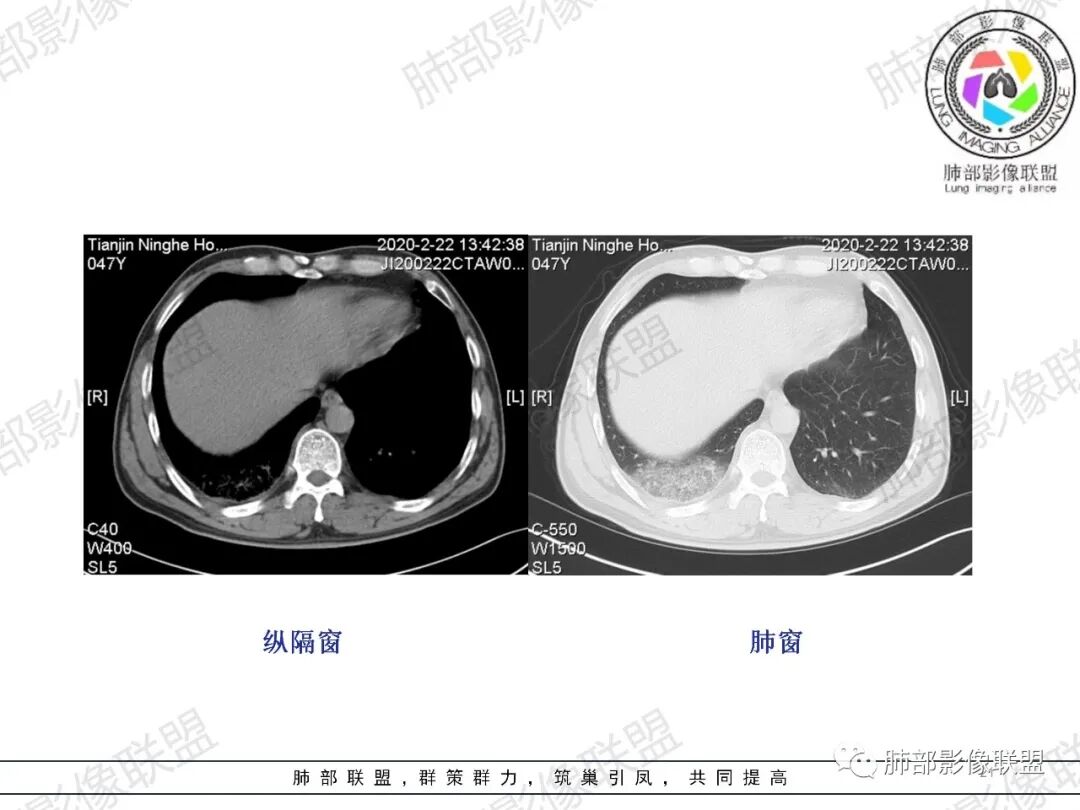

杨泽锋:右肺尖病灶由结节赢、索条影、斑片状影,考虑结核右肺下叶胸膜下楔形斑片状影,因为临床上有胸痛,发热又不明显,首先会想到肺梗,建议增强看看

马春平(张家港市一院胸外科):中年男性、低热、痰血、胸痛 、血象高,右上叶多发结节、疑似空洞、渗出、纤维条索、树芽,右下肺胸膜下与胸膜平行GGO肺泡和小叶间隔增厚,考虑二元论:右上结核、右下肺梗

一切∮随缘:右肺肺尖段多发结节片状高密度影,部分伴有反晕征,边界欠清楚,部分伴有纤维索条,支气管显示欠佳,小叶间隔增厚,周围血管束增粗,(考虑结核可能)右肺下叶胸膜下片状磨玻璃影,与胸膜相贴,与肺组织交界面清楚,实性偏少,考虑:肺栓塞?病毒?OP?

王秀仙:右肺上叶可见结节及斑片影,部分呈反晕征,边缘清晰,右肺下叶后基底段胸膜下磨玻璃样实变影,呈扇形,内部见细网格,右肺上叶考虑结核。右肺下叶考虑肺栓塞,鉴别病毒肺炎。

小兜:男,47岁,胸闷气短入院,一天前无明显诱因胸闷气短伴呼吸困难,夜间出现右侧胸痛,与呼吸及体位有关,曾有一次痰中带血。CT示右肺上叶尖段多发结节,条索影,可见树芽征及反晕征。右肺下叶胸膜下片状密度增高影,宽基底与胸膜相连,成扇形。综合考虑右肺上叶尖段结核可能;右肺下叶肺栓塞?病毒性肺炎?

琦遇:右肺上叶结核基本明确,考虑活动性,有钙化、反晕征、结节、斑片、纤维索条;右肺下胸膜下GGO,内大小网格,胸膜增厚,患者胸痛,咯血,首先考虑PE,下一步增强CTPA以明确

微微笑:右肺上叶斑片、结节、索条影,边缘较清晰,见反晕斑片,考虑结核。右肺下叶宽基底磨玻璃影,网格样改变,胸膜增厚,结合病史,考虑栓塞。

三个石头:右肺上叶结节,斑片,条索,考虑结核。右肺下叶大片磨玻璃,有胸痛,咳血,考虑肺栓塞,建议增强。鉴别病毒肺炎

水晶石头:患者中年男性,胸闷、气促1天。伴右胸痛及痰中带血。否认结核、心脏疾病等病史。查体无特殊。完善血常规白细胞计数、中性粒细胞百分比及C反应蛋白升高。心电图、B超、凝血功能、降钙素原、脑钠肽正常。胸部CT:右肺上叶尖段多发结节、斑片、纤维条索影,见小叶间隔增厚及反晕征。右肺下叶后基底段胸膜下片状磨玻璃影,见小叶内间隔增厚。右侧胸膜增厚,未见明显淋巴结增大。综合考虑右上肺结核病变,右下肺肺栓塞。鉴别病毒性肺炎及恶性病变。

张延军:右肺上叶多发大小不等结节,部分界清,反晕征(+),下叶胸膜下磨玻璃影,纵膈窗似较对称血管细,结合咳血症状,考虑栓塞

小锁:中年男性患者,急性起病,胸闷气喘伴有胸痛,低热,低氧,白细胞增高。CT:右肺上叶斑片状稍高密度影,粟粒样树芽征,有钙化,考虑继发性结核;右肺下叶肺动脉增粗,溶冰征,提示血管来源病变,结合临床病史,考虑肺栓塞。

右上叶,多灶性、多态性,烟花征,结核应该没问题

然后就是右下叶病灶的问题

后基底段,胸膜下,这个没问题吧

我们看看病变的形态、密度、边缘、内部改变

GGO密度

边缘不清

可惜没有重建,楔形?

细网格明显

支气管通畅,壁增厚

血管增粗